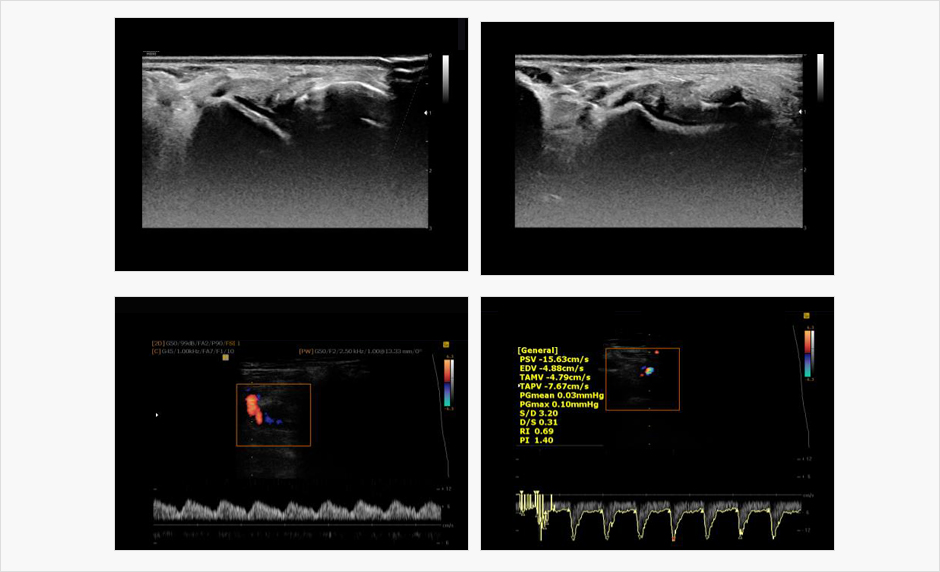

본원에서는 보다 나은 진단을 위해

초음파 장비를 보유하고 있습니다.

본원은 인체에 무해한 초음파 검사를 통해 엑스레이 검사에서는

확인하기 어려운 인대 및 근육 손상과 염증 등의 병변을 확인하여

족부 질환 진단에 이용하고 있습니다.

초음파검사 치료사진